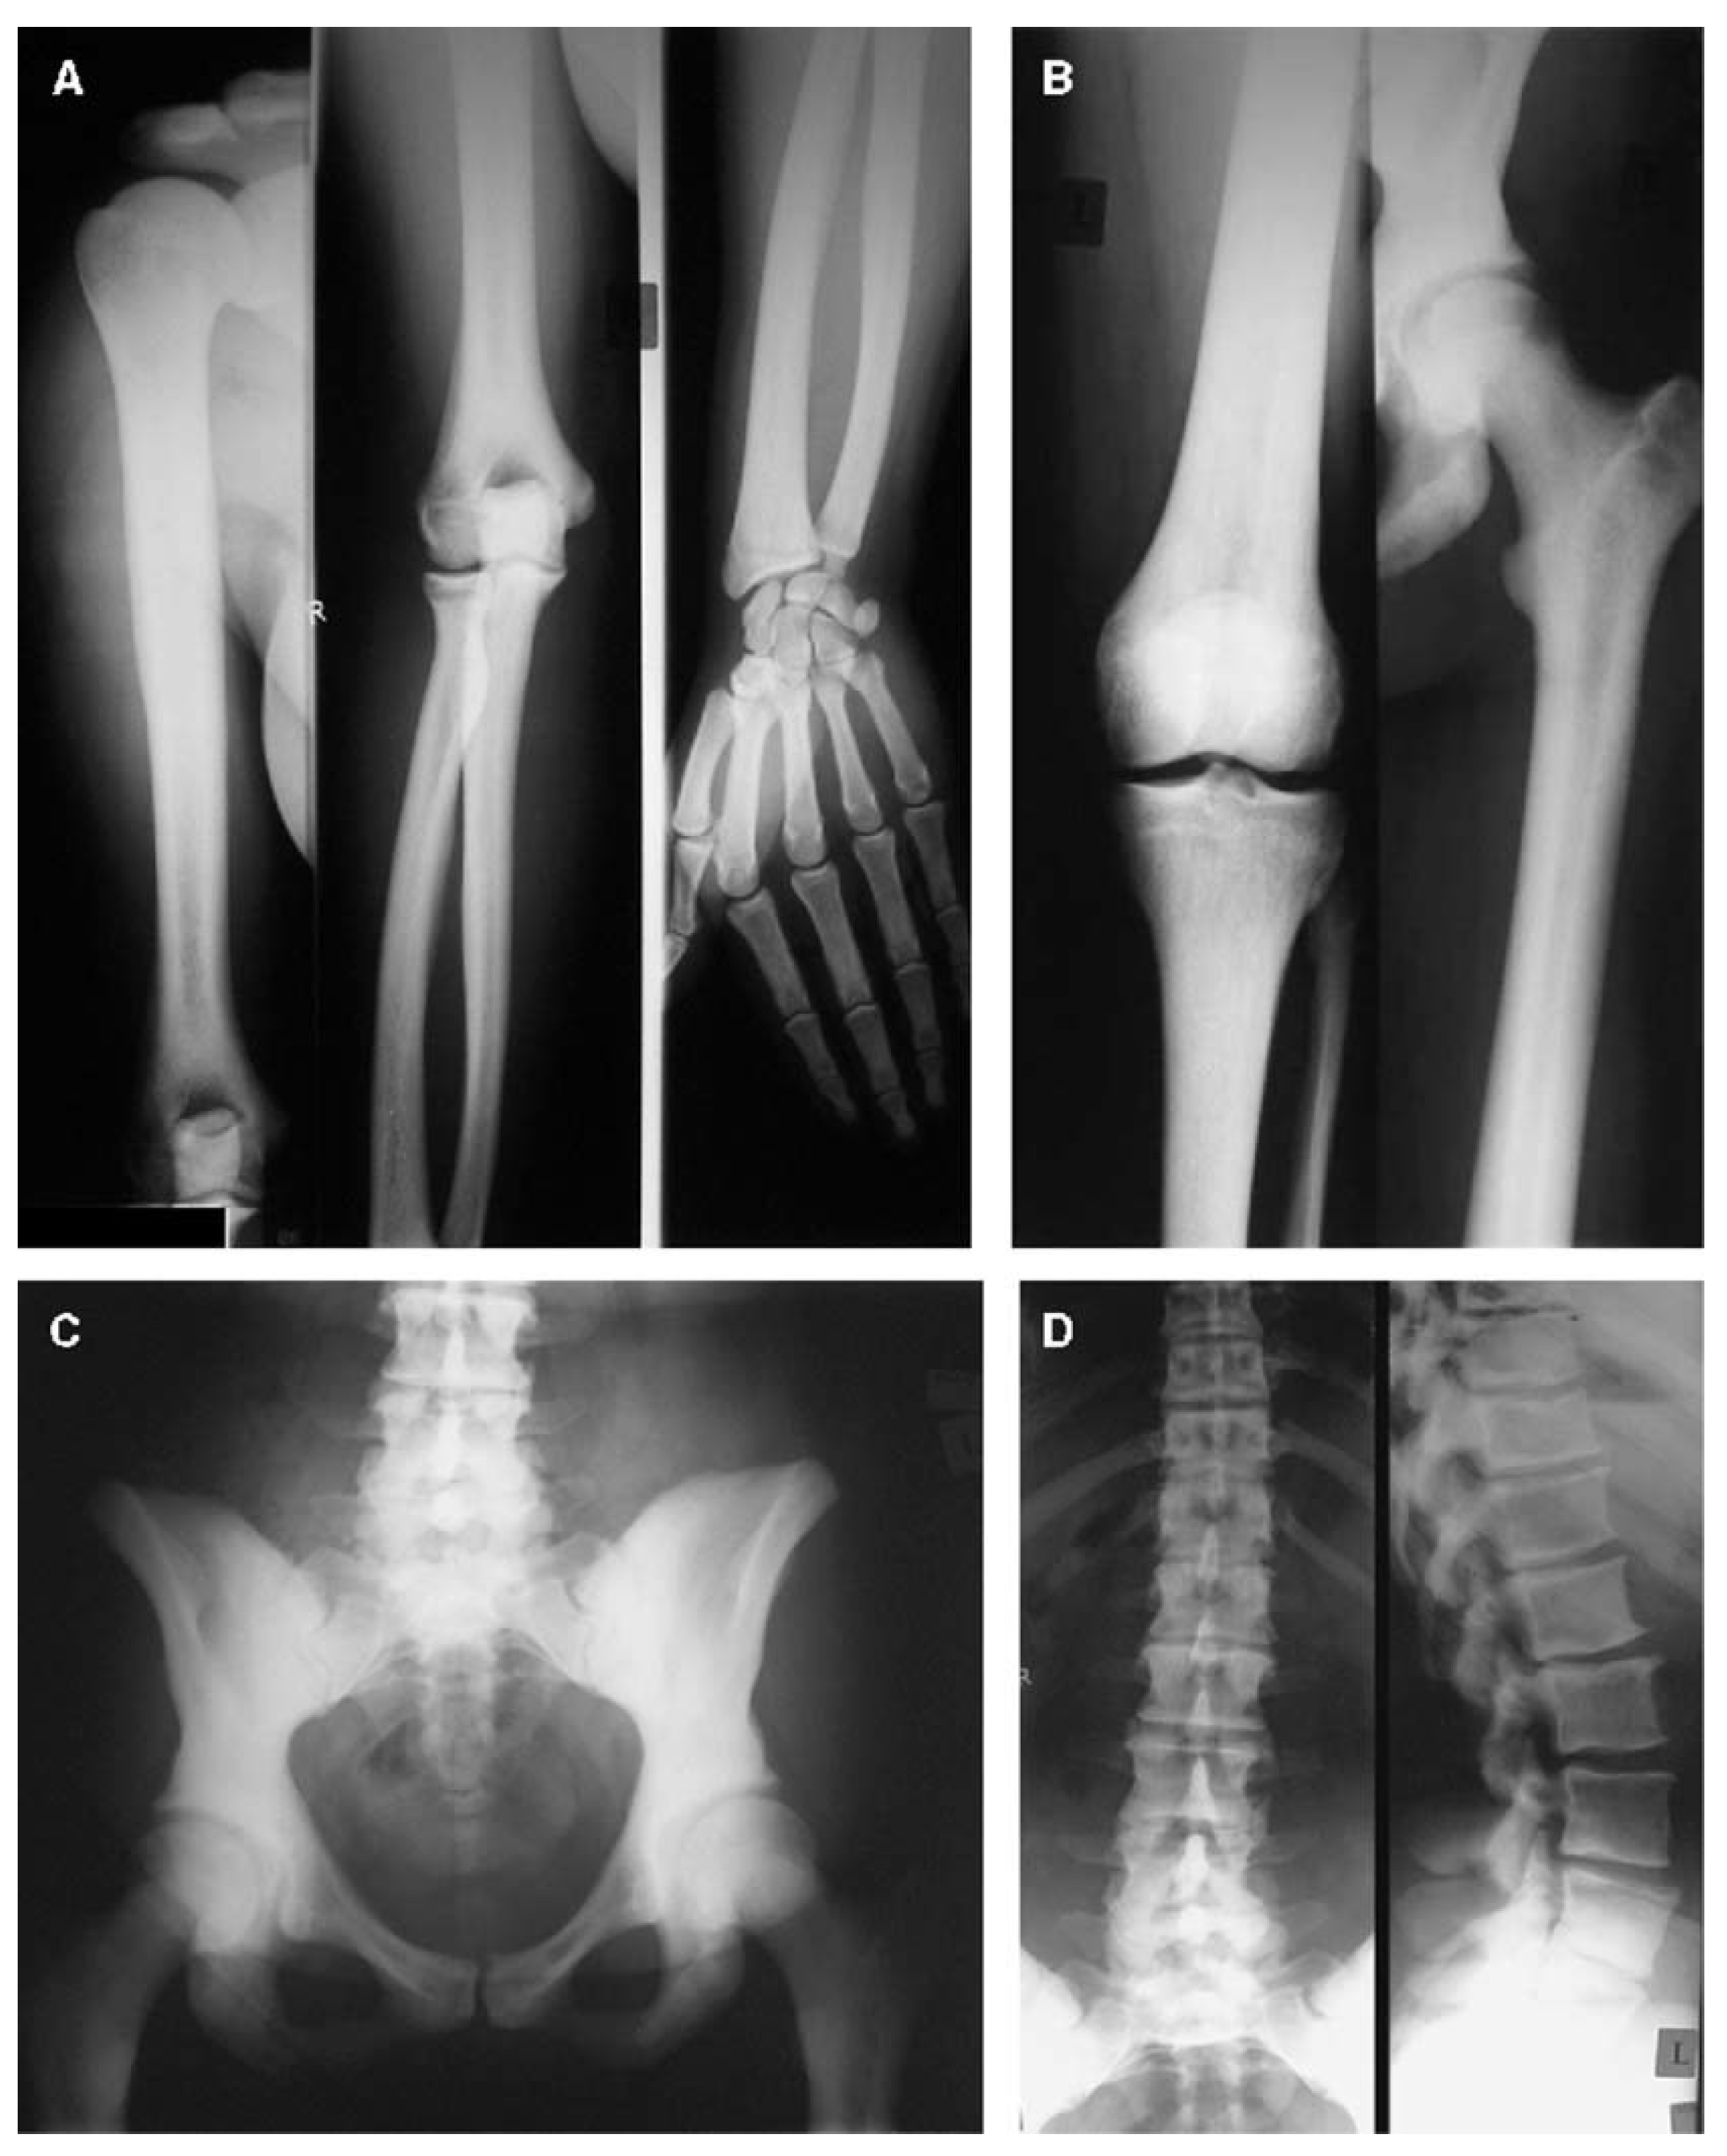

- Littman, J.; Phornphutkul, C.; Saade, C.; Katarincic, J.; Aaron, R. Osteoporosis, Fractures, and Blindness Due to a Missense Mutation in the LRP5 Receptor. Orthop. Res. Rev. 2023, 15, 39–45. [Google Scholar] [CrossRef] [PubMed]

- Zhao, D.; Sun, L.; Zheng, W.; Hu, J.; Zhou, B.; Wang, O.; Jiang, Y.; Xia, W.; Xing, X.; Li, M. Novel mutation in LRP5 gene cause rare osteosclerosis: Cases studies and literature review. Mol. Genet. Genomics. 2023, 298, 683–692. [Google Scholar] [CrossRef]